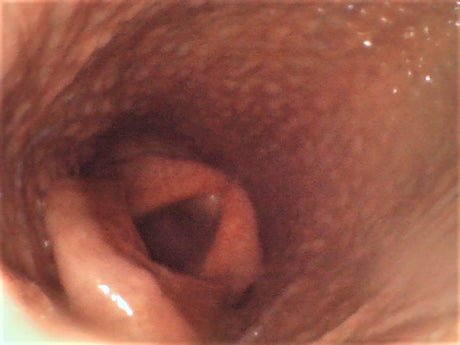

YE-80150M-28 Joystick Articulation Veterinary Endoscope 8mm Diameter 1.5m Probe 4.5" Monitor